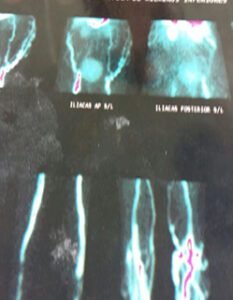

Sistema Respiratorio